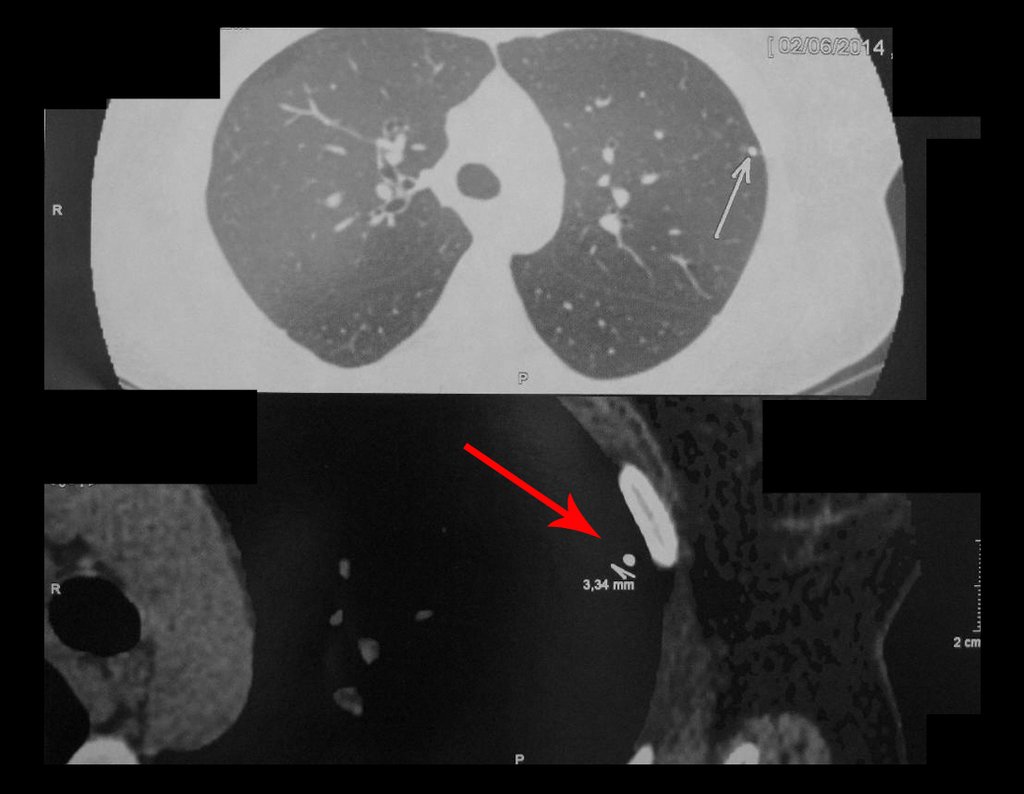

O laudo anátomo patológico diagnosticava tratar-se de osteossarcoma do tipo paraosteal, que devido à manipulação cirúrgica havia invadido o canal medular e já apresentava dois nódulos metastáticos para o pulmão, figuras 1 à 5.

É preciso ressaltar que o paciente em acompanhamento oncológico sofre a cada avaliação de controle. Por isso é prudente previní-los, quanto ao pequeno nódulo pulmonar calcificado do complexo primário da tuberculose, que é normal e esta presente na grande maioria da população. Desta maneira estaremos poupando sofrimento desnecessário tanto ao paciente como aos familiares.